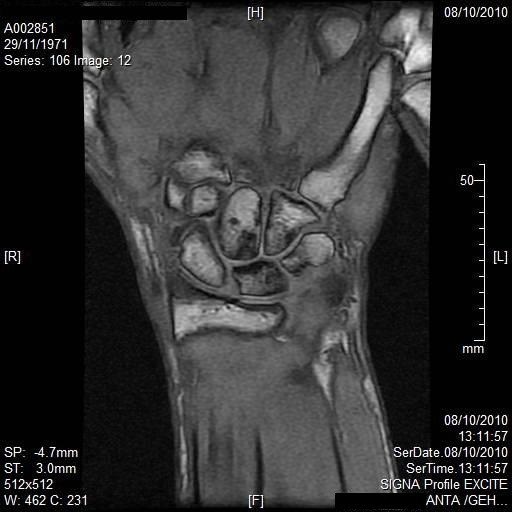

La resonancia magnética combina la tecnología de la computación, un campo magnético y ondas de radio para producir una imagen bidimensional de un “corte” de la anatomía del paciente. Este procedimiento no expone al paciente a radiaciones y las ondas de radio son inofensivas.

A diferencia de los barridos de la Tomografía Computada y las imágenes de rayos X, la resonancia magnética produce imágenes altamente detalladas que son aptas para la identificación de patologías de los tejidos blandos. Otra ventaja de la resonancia magnética es que puede producir imágenes de diferentes planos anatómicos, por lo que hace posible el estudio de la anatomía desde diferentes ángulos.